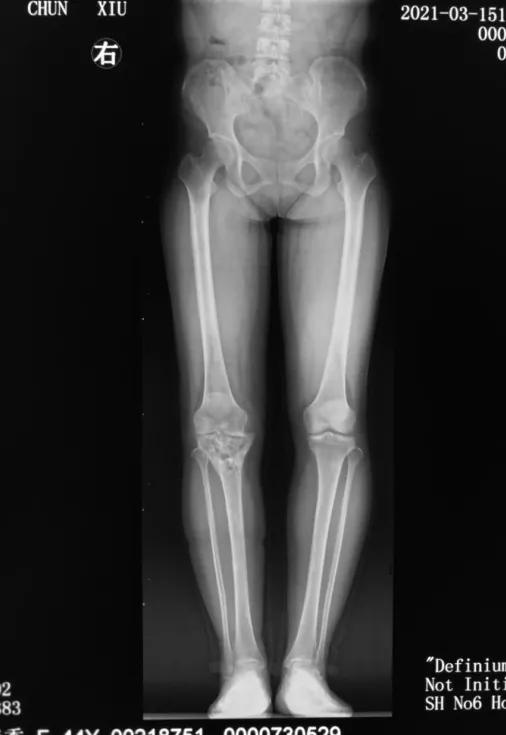

患者杨女士44岁,3年前意外摔伤,右侧膝关节骨折,胫骨平台畸形愈合,导致膝内翻畸形。

经过详细问诊以及X线检查,发现杨女士胫骨平台畸形愈合,平台大于股骨远端,膝关节对合不佳。刘万军主任决定行胫骨内侧髁截骨(TCVO),经过一系列周密的术前计划,刘主任为杨女士术前量身制作截骨模板,术后杨女士当天便可以下床活动,第二天就可以出院了,看见自己的腿由弯变直,杨女士的脸上露出了久违的笑容,对刘万军主任团队高超的医术赞不绝口。

术前

膝内翻俗称“O型腿”,表现为双脚并拢时,双膝不能靠拢。在X线正位片上显示膝关节内外侧间隙不等宽,内侧间隙明显变窄。